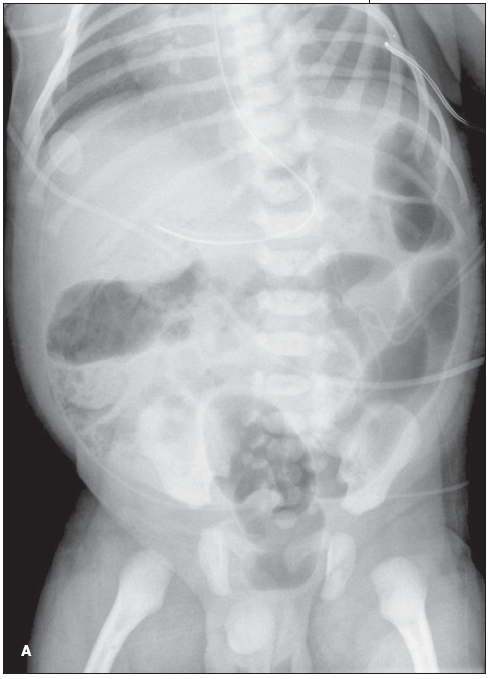

A 30-hour-old boy--born to a 36-year-old gravida 3, para 3, at full term via a spontaneous vaginal delivery--was noted to a have a mildly distended abdomen while in the newborn nursery.